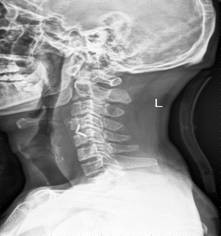

中年男性41岁,因“行走不便2年,加重伴双手麻木2周”之主诉入院,症状主要为:颈部疼痛、僵硬,双下肢无力、行走不稳,双手麻木,协调性差,右手握笔困难。入院查体:步态不稳,C3-C7压痛、叩击痛,肢痛温觉减退,双上肢肢肌力5-级,双下肢肌力4-级,肌张力增高,双下肢腱反射亢进,病理征(+),行颈前路小切口突出椎间盘切除、前路颈椎桥形锁定植骨融合(ROI-C假体),无需前路钢板,术后四肢麻木明显缓解,右上肢精细动作明确增强,可写字,行走不稳消失,肌力基本正常,颈部活动度无明显受限。(图1、图2)

图2:术后颈椎X线提示颈椎桥形锁定融合居中,椎间隙高度恢复正常,融合良好。